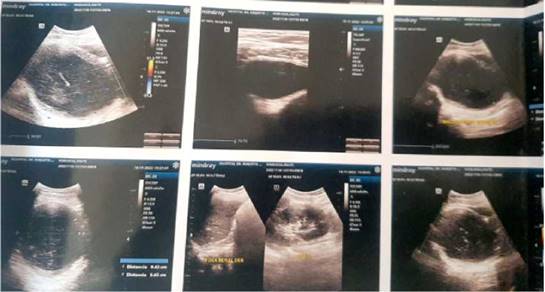

Figura 2: Ecografía abdominal, Lo más llamativo se evidencia la ausencia del riñón derecho en relación a agenesia renal con aumento morfológico fisiologico compensatorio del riñón izquierdo. En cavidad pélvica se observa nuevamente aumento de la colección anecoica en cavidad endometrial y vaginal derecha sugestivo de hematocolpos (vagina obstruida ipsilateral) ambos correspondientes a probable OHVIRA. (malformación uterina caracterizada por útero didelfo, hemivagina ciega total o parcial y agenesia renal ipsilateral). Escaso liquido libre en FID sin visualización del apéndice cecal a corroborar con clínica y laboratorios